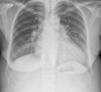

Da investigação inicial do quadro clínico, realça-se: analiticamente anemia, D-dímeros e marcadores de necrose miocárdica negativos, com aumento do pro-BNP (Tabela 1) e radiografia do tórax com aumento do índice cardiotorácico (Figura 2).